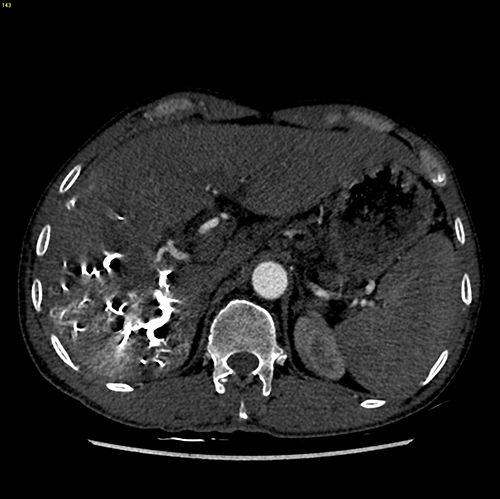

右肝癌---右三肝切除

介入后2周